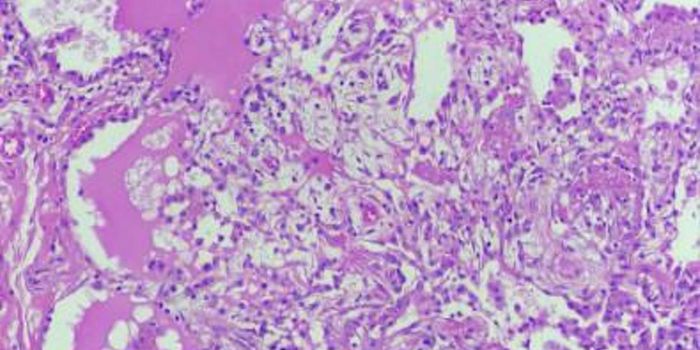

OCT 10, 2021Cell & Molecular BiologyThere is a well-known causal connection between smoking and lung cancer, and most research on lung cancer has been focus ...